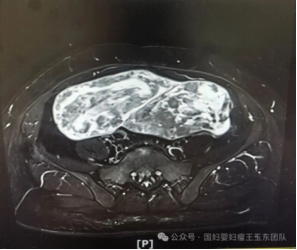

来自外省的李女士,体型偏肥胖,近两年发现子宫肌瘤增大明显并引起了严重的压迫症状。磁共振检查提示多发性子宫肌瘤,合并左侧宫旁阔韧带肌瘤伴变性可能,其最长径达到20多厘米。同时,既往有剖宫产史、右卵巢子宫内膜异位囊肿剥除术史,存在的盆腹腔粘连均使手术难度进一步加大。